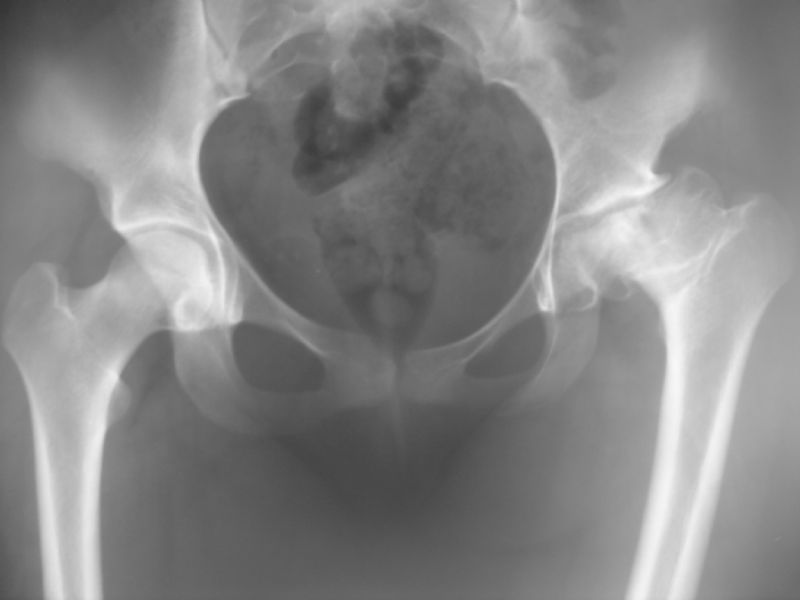

Total Kalça Protezi Örnek Olgular